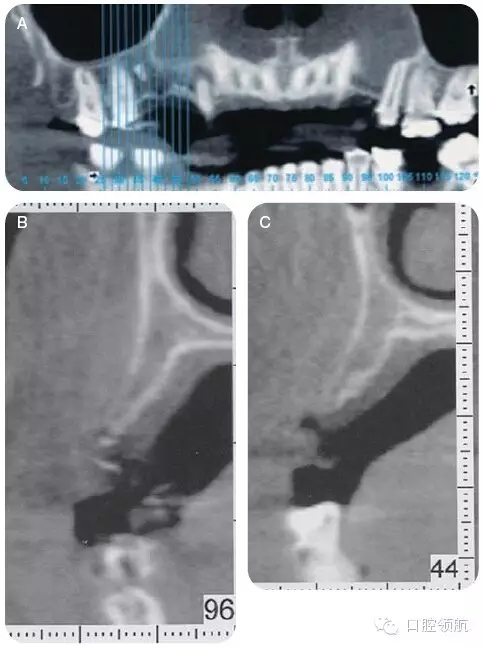

咨詢修復、牙體牙髓及正畸科,制訂詳細的治療計劃。行錐形束CT檢查上頜牙弓,以更好地了解缺損處牙槽嵴的形態(tài)及和上頜竇的鄰接關系(圖4)。

CT顯示牙槽嵴的垂直距離足夠,為更好地植入種植體,尚需有6~7mm的骨寬度。該區(qū)域的最終治療計劃包括:引導骨再生,修復以及咬合重建,包括#4-X-6種植體支持的局部固定義齒。

圖4 (A~C)CT檢查,顯示14號牙(左上頜第一磨牙)的牙槽嵴水平缺損。